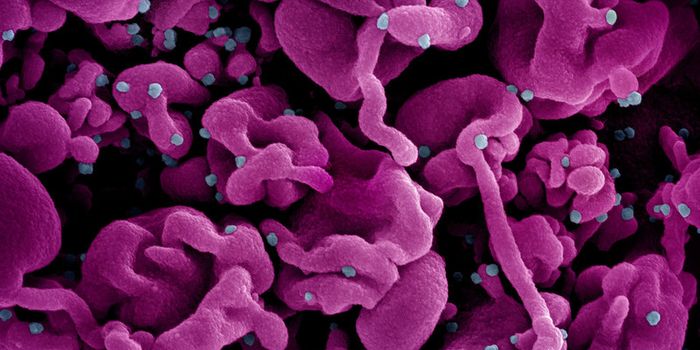

JUL 11, 2021MicrobiologyIn October 2020, what's now called the Delta variant of SARS-CoV-2 was first detected. It's now the most prevalent strai ...

NOV 01, 2021Cell & Molecular BiologyResearchers have learned a lot about the SARS-CoV-2 virus since the start of the COVID-19 pandemic. We know that he viru ...

MAY 06, 2020Cell & Molecular BiologyOnce thought to cause symptoms that primarily affect the respiratory system, there has been evidence that the virus can ...